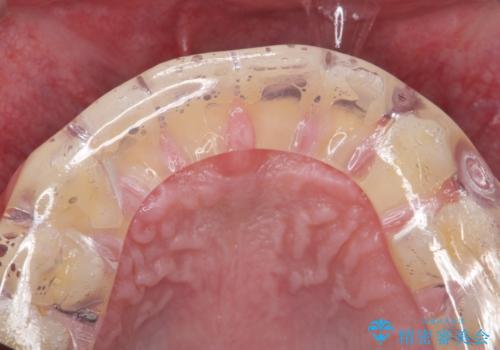

- 歯軋りが気になるとの事で来院。

歯が割れたりするのを予防したいとの事でしたのでナイトガードを作製しました。

- 自費ナイトガード 3.3万円費用は治療当時の料金となります

ナイトガードを使用することにより歯が割れるリスクが低くなります。